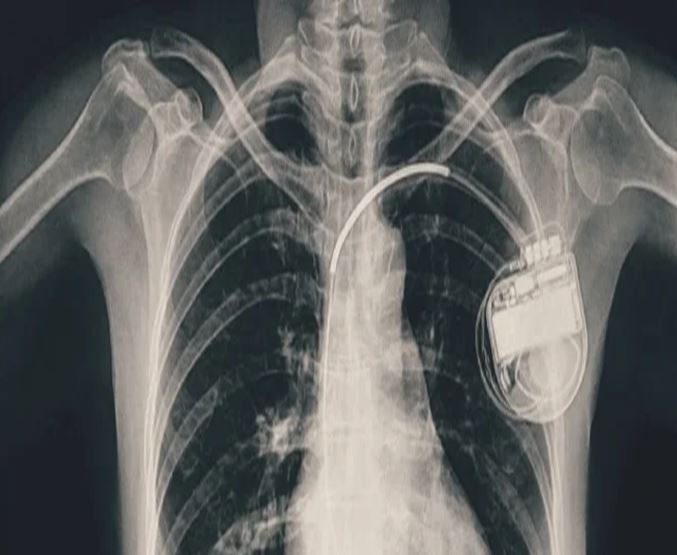

भोपाल। भोपाल मेमोरियल अस्पताल एवं अनुसंधान केंद्र (बीएमएचआरसी) के कार्डियोलॉजी विभाग ने एक दुर्लभ और चुनौतीपूर्ण चिकित्सा उपलब्धि हासिल की है। यहां 13 वर्ष की गैस पीड़ित आश्रित बालिका को इमरजेंसी में डुअल चेंबर पेसमेकर लगाकर उसकी जान बचाई गई। अब बालिका की हालत बेहतर है और उसे अस्पताल से छुट्टी दे दी गई है। यह प्रक्रिया सहायक प्रोफेसर डॉ. अमन चतुर्वेदी और उनकी टीम द्वारा सफलतापूर्वक की गई।

तीन वर्ष की आयु में दिल में था छेद

बीएमएचआरसी के कार्डियोलॉजी विभाग के सहायक प्रोफेसर डॉ. अमन चतुर्वेदी ने बताया कि यह मरीज जन्म से ही हृदय रोग से पीड़ित थी। तीन वर्ष की आयु में उसके दिल में छेद (congenital heart defect) का ऑपरेशन किया गया था। ऑपरेशन के बाद उसे हार्ट ब्लॉक हो गया यानी हृदय की धड़कन असामान्य रूप से धीमी हो गई। इसके कारण उसे चक्कर आना, आंखों के सामने अंधेरा छा जाना जैसी परेशानियां होने लगीं।हार्ट ब्लॉक की स्थिति में, बचपन में ही उसे एपिकार्डियल पेसिंग (epicardial pacing) डिवाइस लगाई गई। इस प्रक्रिया में पेसमेकर के तार हृदय की बाहरी सतह पर लगाए जाते हैं, जो आमतौर पर छोटे बच्चों में अपनाई जाती है, क्योंकि उनके हृदय का आकार छोटा होता है। इस डिवाइस की आयु लगभग 10 वर्ष होती है। डिवाइस की अवधि पूरी होने के बाद हाल ही में मरीज को फिर से वही लक्षण होने लगे। बीएमएचआरसी में जांच के बाद यह स्पष्ट हुआ कि अब उसे एक स्थायी और अधिक उन्नत पेसमेकर की आवश्यकता है। आपातकालीन स्थिति में टीम ने सफलतापूर्वक डुअल चेंबर पेसमेकर प्रत्यारोपित किया। इस जीवनरक्षक प्रक्रिया को अंजाम देने वाली टीम में कार्डियोलॉजी विभाग के सहायक प्रोफेसर डॉ. कपिलकांत त्रिपाठी, डॉ. नुपुर गोयल, मेडिकल ऑफिसर डॉ. अनुराग ठाकुर एवं अन्य सदस्य शामिल थे।

क्या होता है डुअल चेंबर पेसमेकर?

पेसमेकर एक छोटा उपकरण होता है, जो दिल की धड़कन को नियंत्रित करता है। यह दिल को सही गति से धड़कने में मदद करता है। सिंगल चेंबर पेसमेकर हार्ट के सिर्फ एक चेंबर को इलैक्ट्रिक सिग्नल देता है, जबकि डुअल चेंबर पेसमेकर दिल के दो भागों-ऊपरी (एट्रियम) और निचले (वेन्ट्रिकल) चेंबरों को दोनों को सिग्नल भेजता है, जिससे दिल की धड़कन और भी प्राकृतिक तरीके से चलती है। बच्ची के मामले में डुअल चेंबर पेसमेकर इसलिए लगाया गया क्योंकि उसकी स्थिति अधिक जटिल थी और बेहतर तालमेल के लिए दोनों चेंबर तक एकसाथ सिग्नल देना ज़रूरी था।